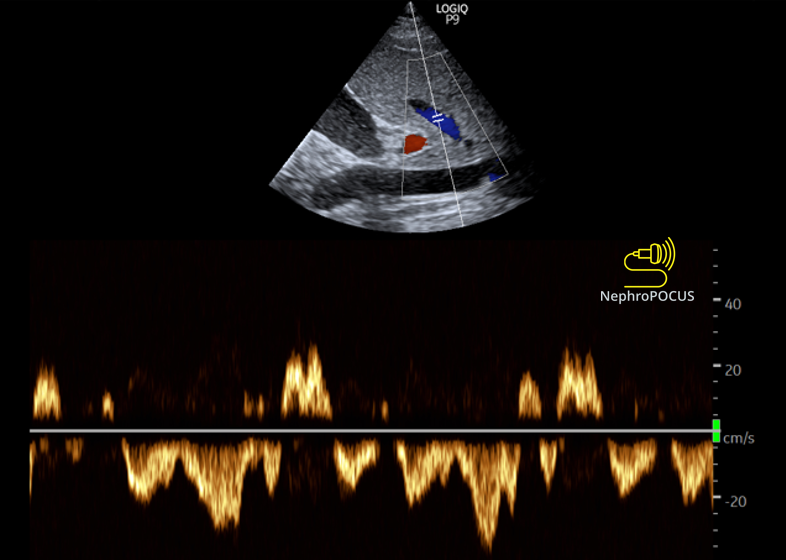

ICU Stories: 20 years' old pt, previously healthy, presented to the ED w 2 wks' of dyspnea /dizziness/ chills-sweats / cough-anorexia-fatigue. BP 130/70, temp 38 deg C. Labs: WBC 9.0k (normal diff), Hct 39, PLT 350k, creat 0.9. CXR clear. COVID-flu: (-) Admitted due to this: